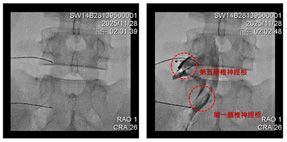

Advanced

biplane fluoroscopy (dual-plane X-ray) to perform highly precise image-guided

injections

After

guiding the needle to the correct location under X-ray, contrast is used for

confirmation before performing the targeted treatment